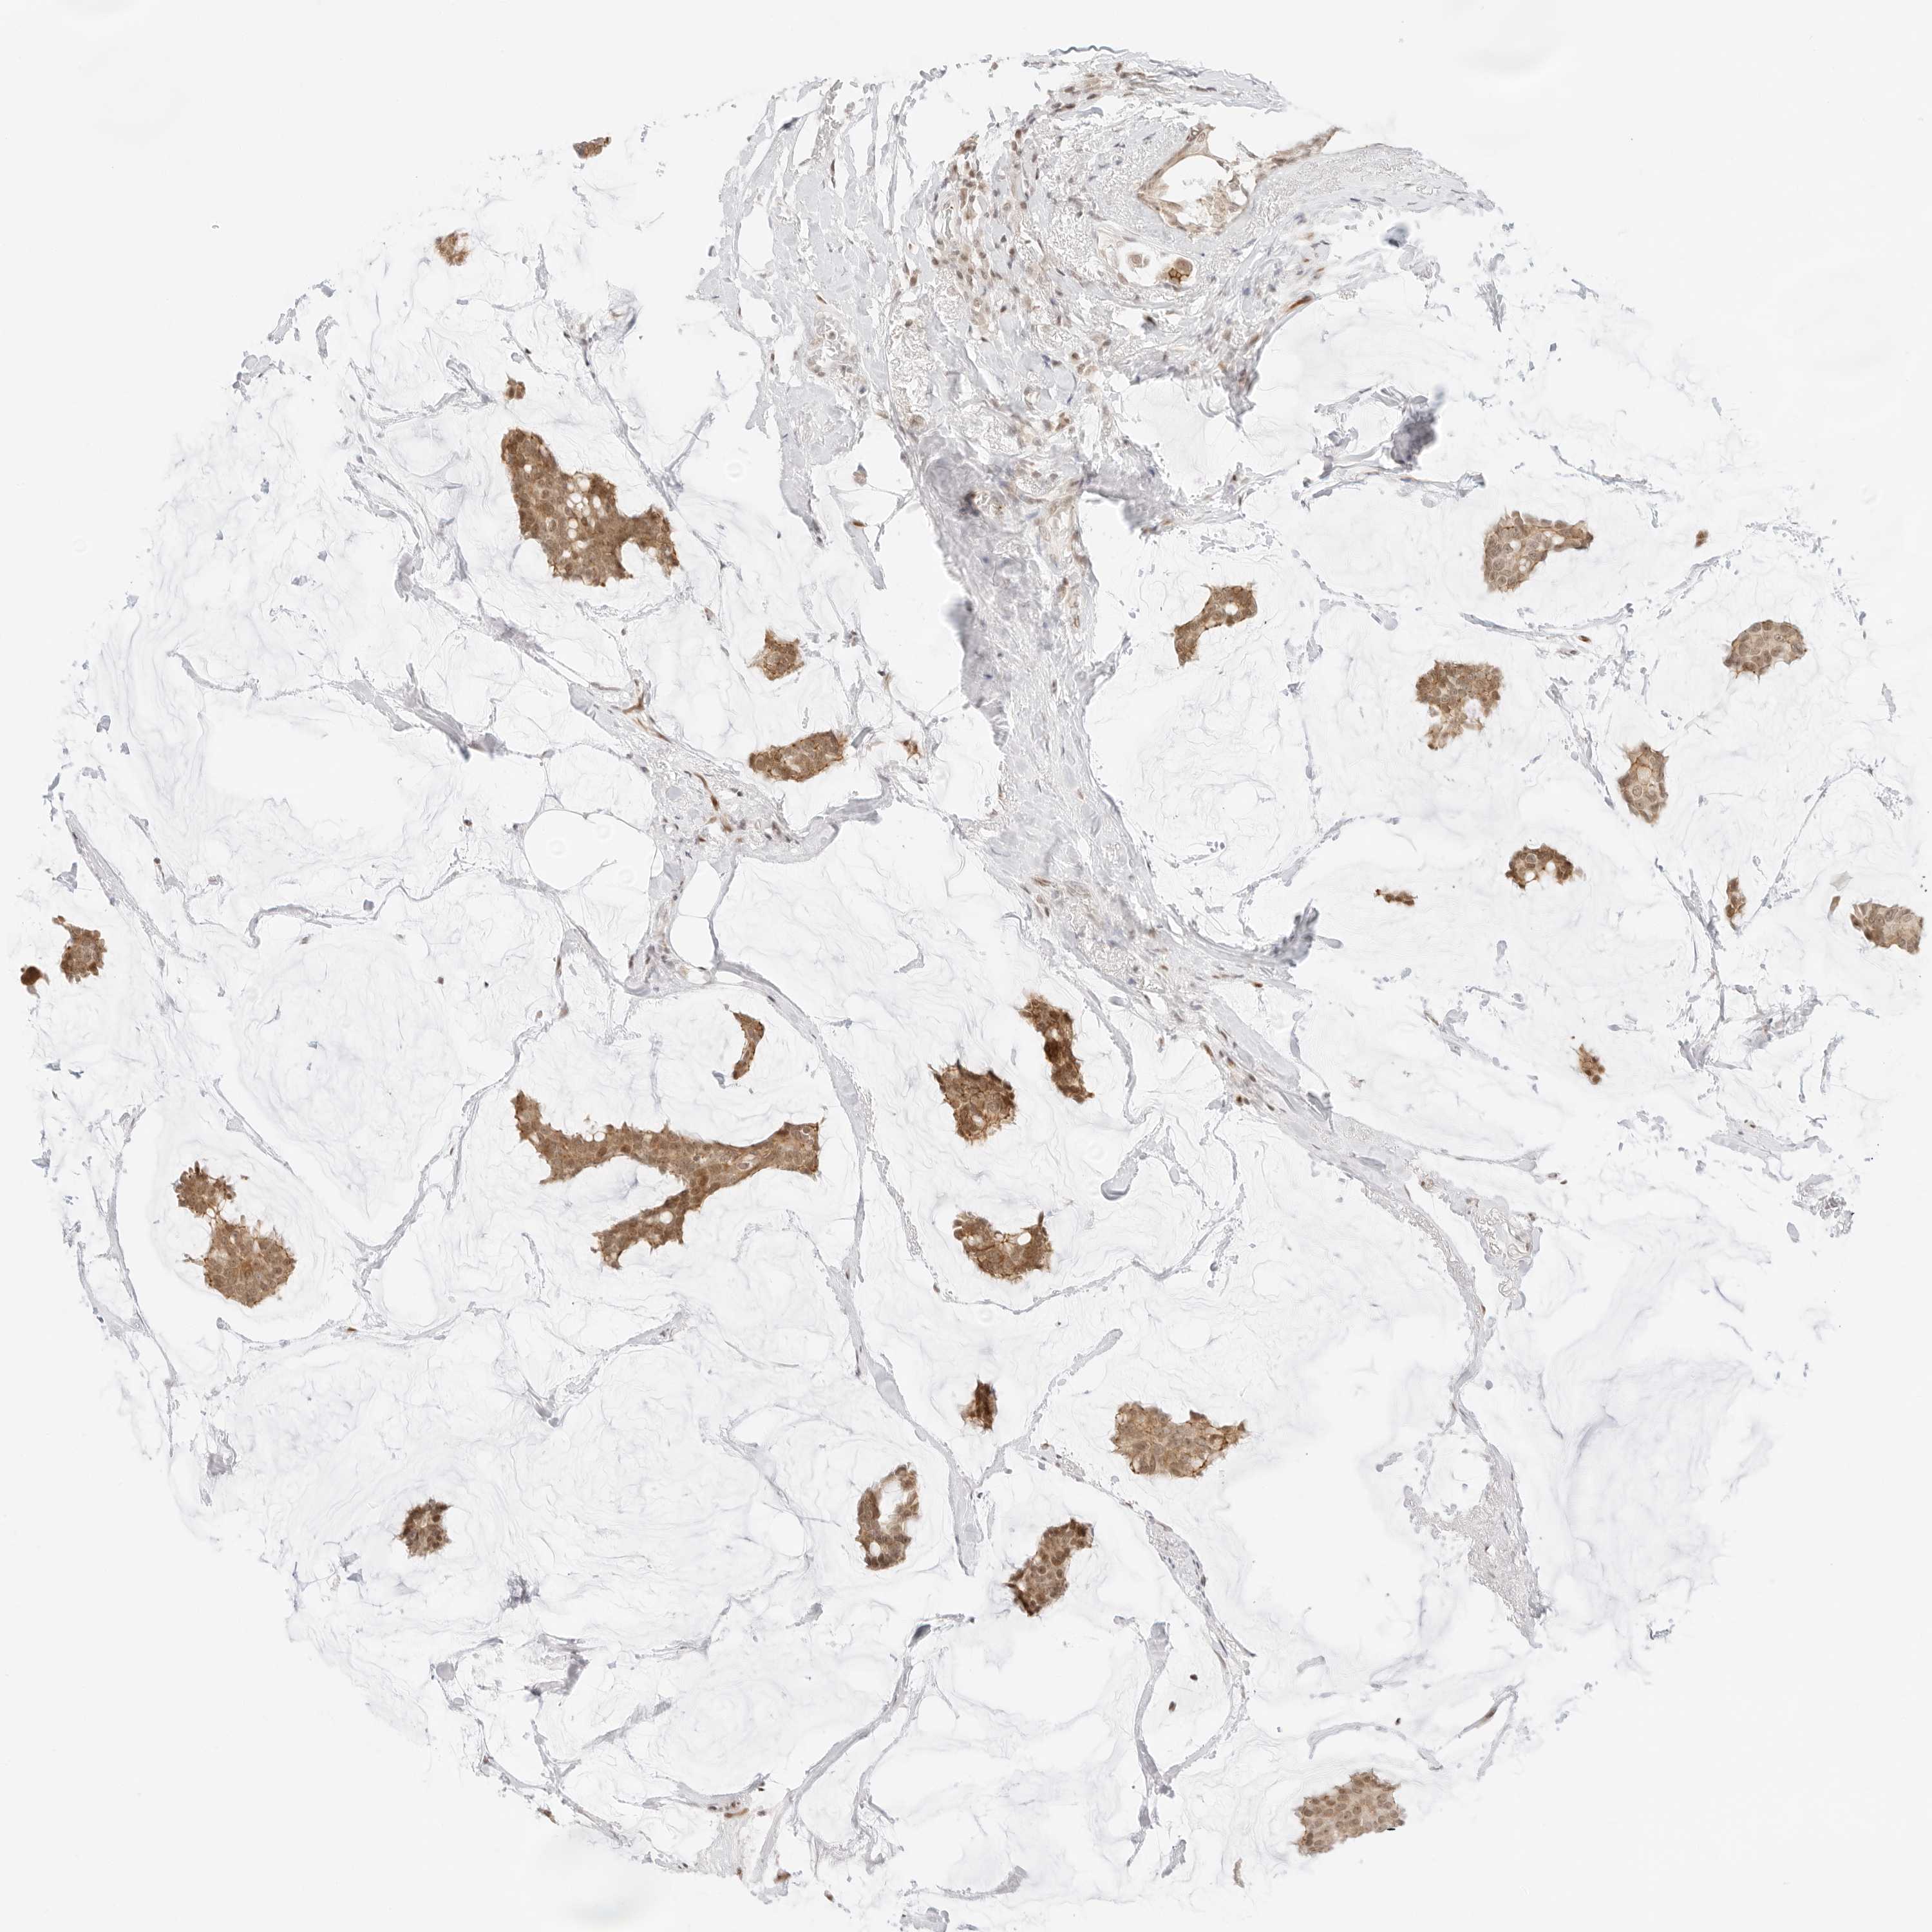

CANCER BREAST CANCER Show tissue menu

BRCA TCGA BRCA VALIDATION PROTEIN EXPRESSION